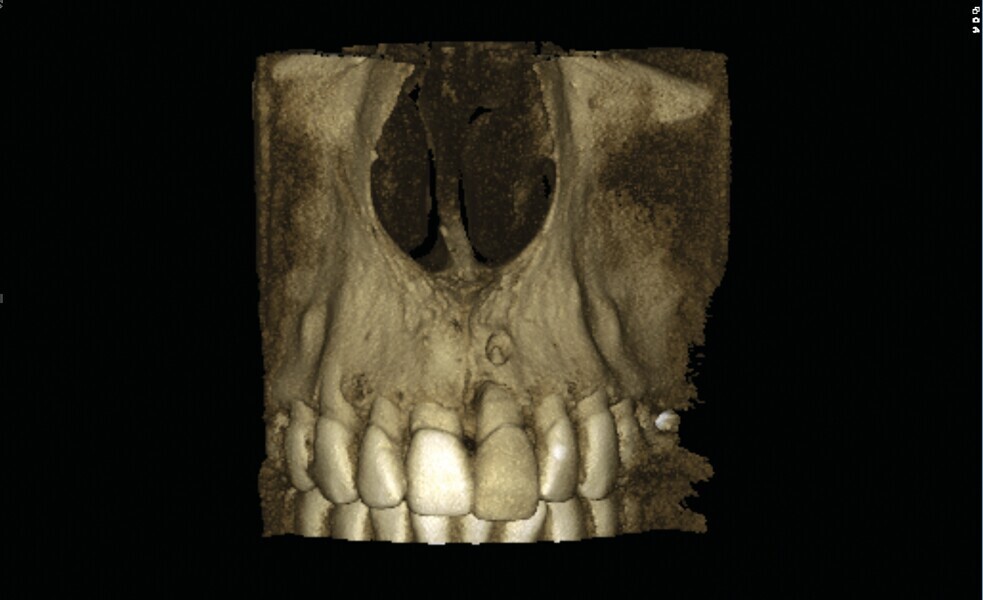

Fig. 2 : Image CBCT en 3D des structures osseuses (b). La lésion périapicale est mise en évidence.

Une fistule avec écoulement purulent est présente en regard de l’apex de la dent. Une tomodensitométrie volumique a faisceau conique (CBCT) est réalisée pour évaluer l’environnement péri-dentaire : l’épaisseur de l’os vestibulaire, la forme de l’alvéole et la position de la racine sur le plan sagittal (Figs. 2–3). Une fracture radiculaire est mise en évidence.

L’endodontiste chez qui la patiente a d’abord été référée a émis un pronostic peu favorable en raison d’une déhiscence osseuse importante en vestibulaire, associée à une fenestration au niveau de l’apex. L’espace inter occlusal est réduit, avec un profond recouvrement incisif. La décision de ne pas conserver cette dent est alors prise. Le choix se porte vers une restauration unitaire implanto-portée.

Dans le cas de la patiente, les tissus mous sont bien positionnés : la dent a subi une égression, mais aucune récession n’est présente. L’os vestibulaire est partiellement absent et classe l’alvéole dans le type II selon Elian et al.2